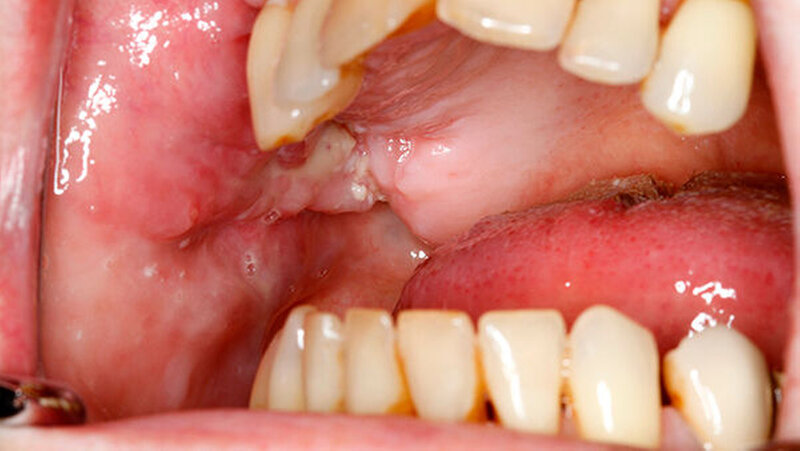

Im Mundbereich ist das Nähen schwierig

"In Tierversuchen am Schweinemodell mit kollagenbasierten Wundauflagen war das Heilungsverhalten positiv, wobei diese Versuche statistisch noch nicht abgesichert sind", berichtete Wehner im Gespräch mit den zm. "In der Oralchirurgie und der Mund-, Kiefer-, Gesichtschirurgie könnte dieses Verfahren eine effektive Lösung für die Patientenversorgung darstellen, weil im Mundbereich aufgrund der anatomischen Verhältnisse, der Keimbelastung wie auch der Feuchtigkeit eine adäquate Wundabdeckung oft nur schwierig möglich ist", sagte Projektpartner Univ.-Prof. Dr. Dr. Ralf Smeets von der Klinik und Poliklinik für Mund-, Kiefer- und Gesichtschirurgie am UKE Hamburg-Eppendorf.

Nach Angaben von Smeets könnte der lasergestützte Wundverschluss beispielsweise nach Tumoroperationen sowie Traumata eingesetzt werden. Aber auch im Bereich der Implantologie eigne sich das Verfahren.